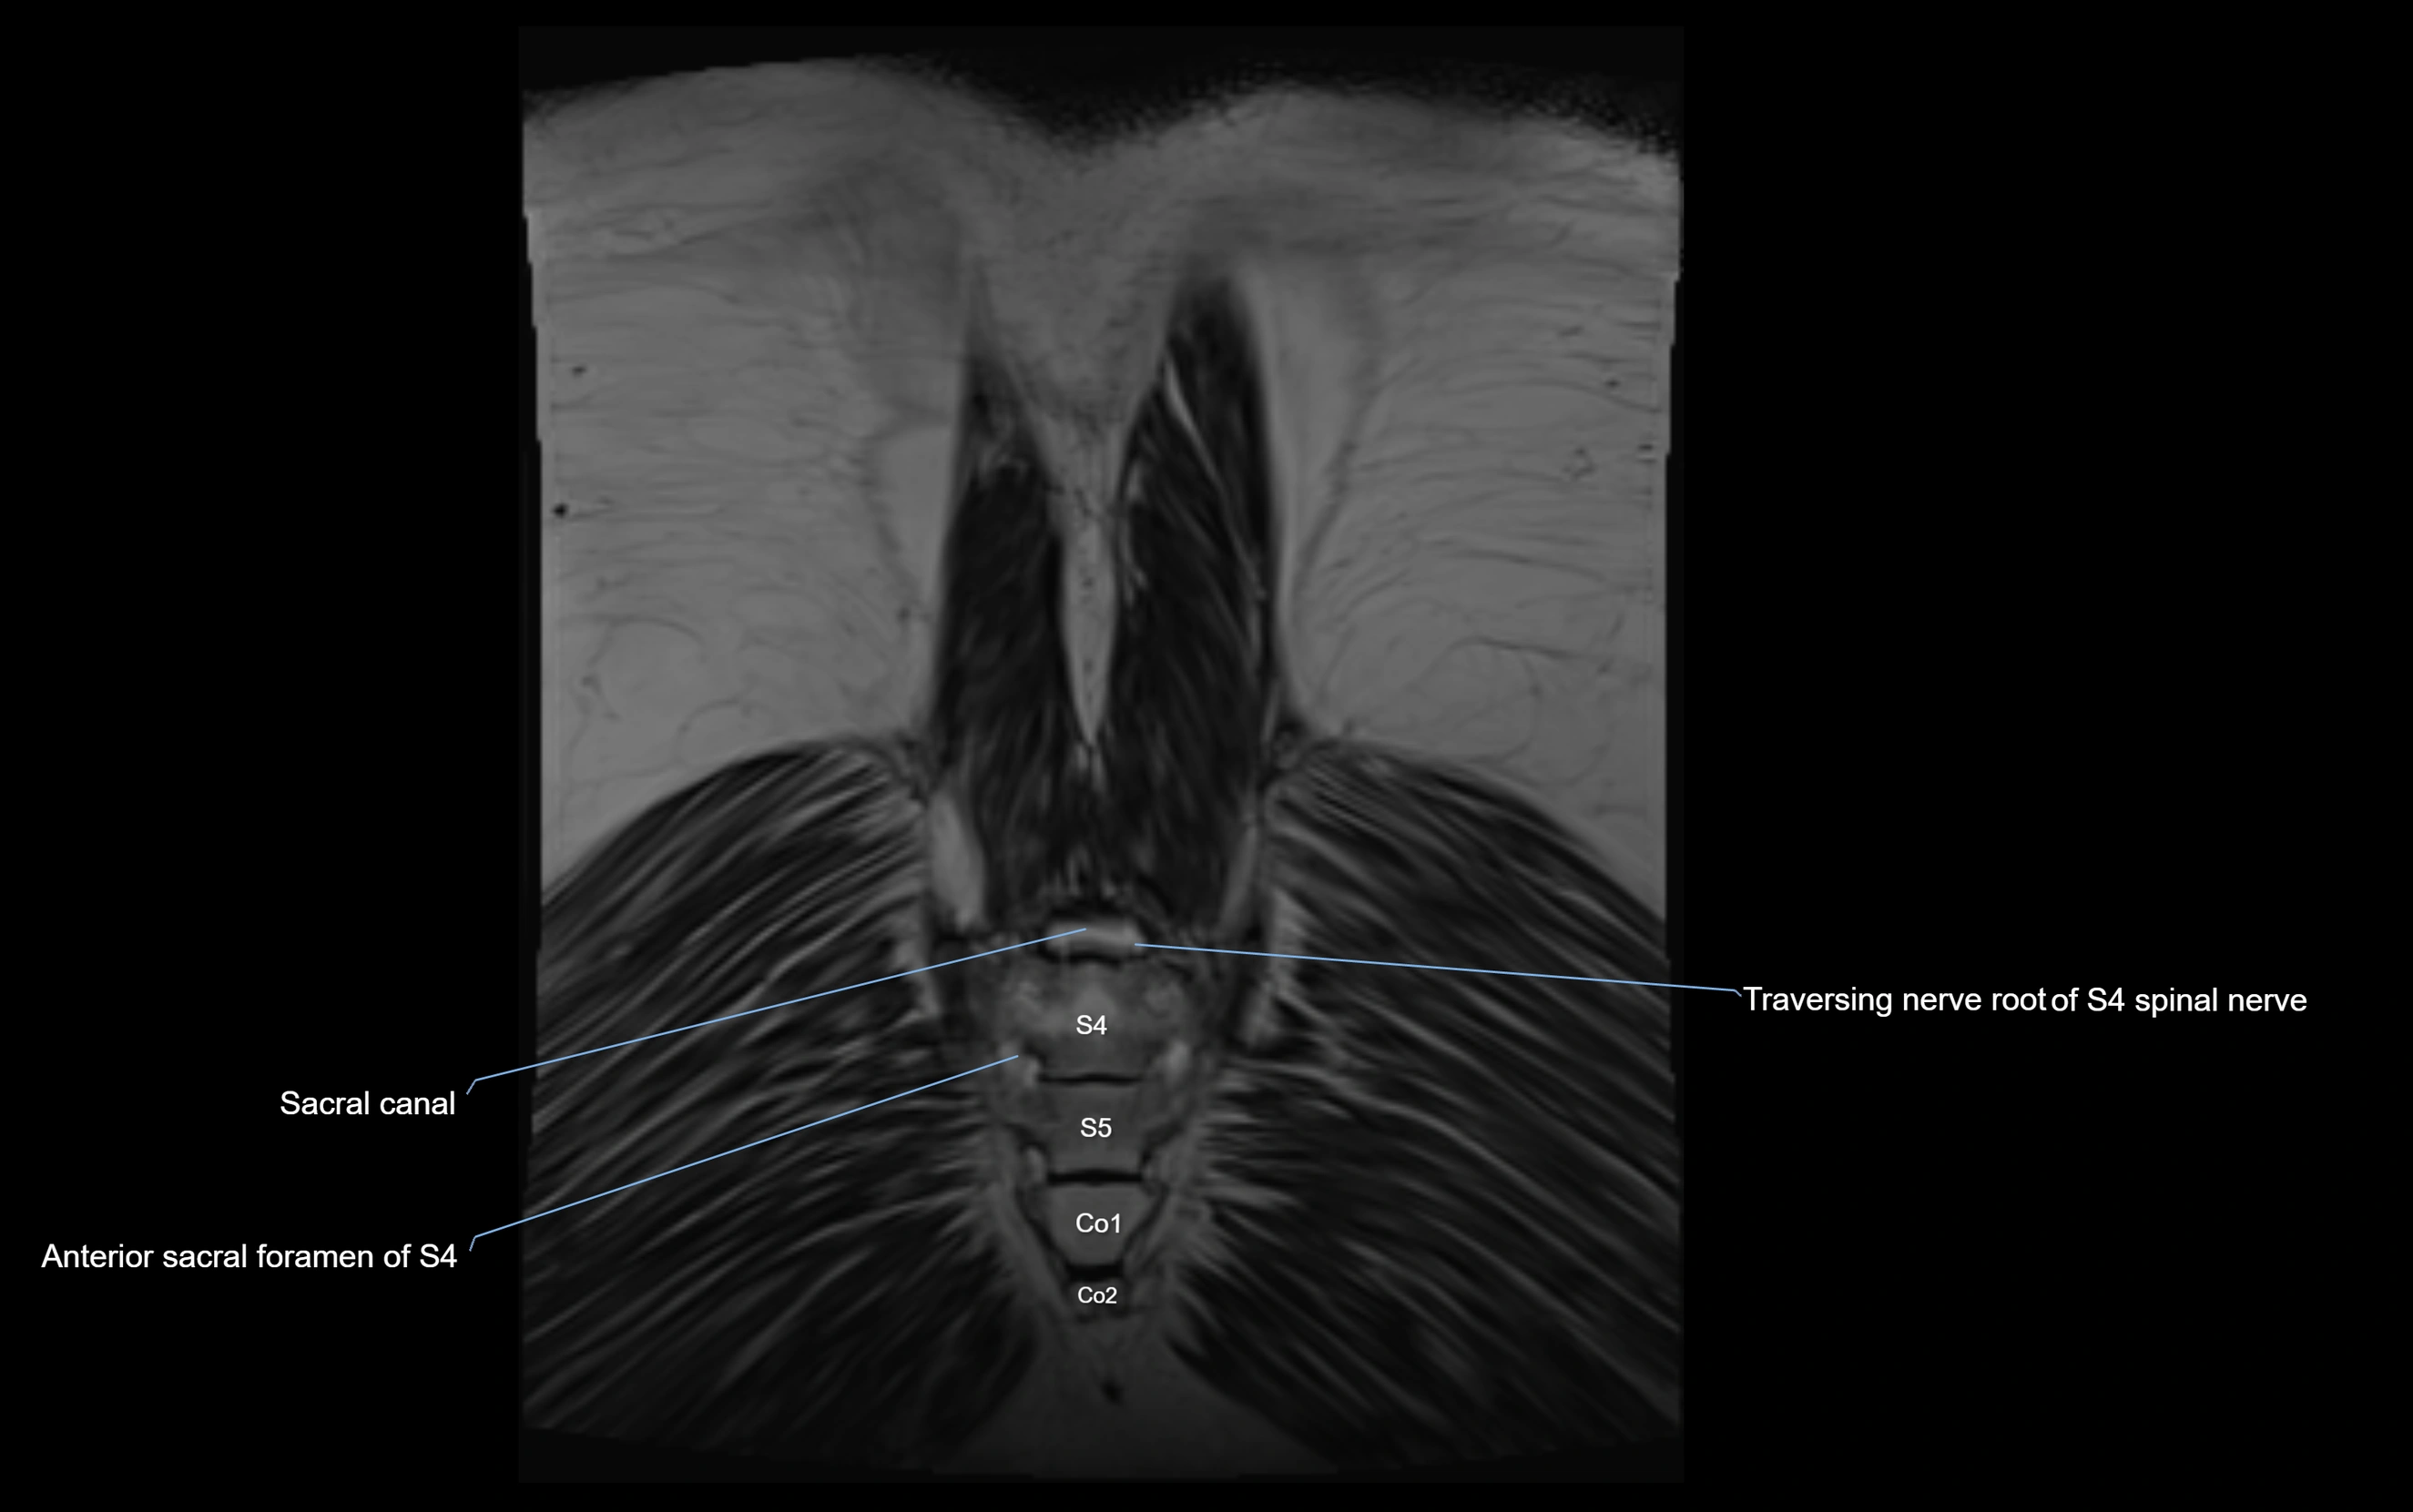

MRI Appearance

T1-weighted images:

• Nerve appears as a very thin low-to-intermediate signal intensity structure

• Surrounded by bright fat, aiding visualization

T2-weighted images:

• Nerve shows intermediate to mildly hyperintense signal compared to muscle

• Pathological involvement appears brighter

STIR (Short Tau Inversion Recovery):

• Normal nerve appears dark

• Inflamed or entrapped nerve appears bright hyperintense

T1 Fat-Sat Post-Contrast:

• Normal nerve enhances minimally

• Pathologic nerve (neuritis, entrapment, tumor infiltration) shows focal or diffuse enhancement

3D T2 SPACE / CISS:

• Nerve appears intermediate to mildly hyperintense compared to muscle

• Surrounded by bright fat or CSF, improving visualization

• Best sequence for mapping small pelvic nerves such as the anococcygeal